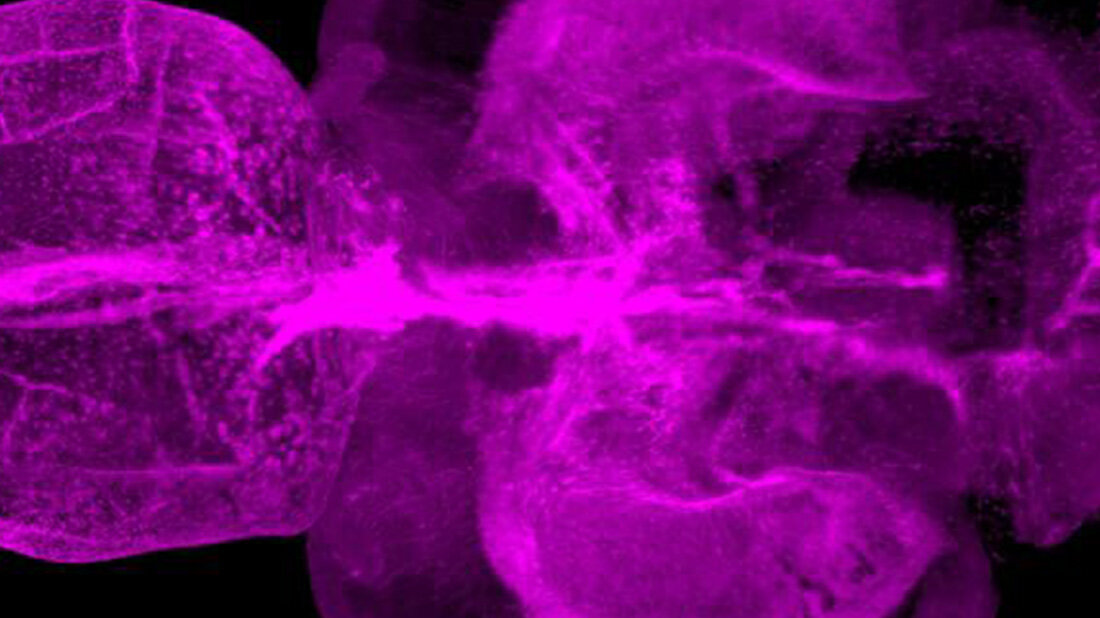

Im Gegensatz zu Säugetieren ist das Zentralnervensystem (ZNS) von Zebrafischen außergewöhnlich regenerationsfähig. Bei Verletzungen entstehen unter anderem langlebige Neuronen aus neuralen Stammzellen. Darüber hinaus führen ZNS-Verletzungen bei Zebrafischen nur zu einer vorübergehenden Reaktivität von Gliazellen, was die Integration von Nervenzellen in verletzten Regionen des Gewebes erleichtert. „Die Idee war, Unterschiede zwischen Zebrafischen und Säugetieren herauszuarbeiten, um zu verstehen, welche Signalwege im menschlichen Gehirn die Regeneration hemmen – und wie wir hier vielleicht eingreifen können“, sagt Ninkovic. Die Wissenschaftlerinnen und Wissenschaftler erzeugten gezielt ZNS-Läsionen in Zebrafischen, worauf Mikroglia aktiviert wurden. Gleichzeitig fanden die Forschenden in den Läsionen eine Ansammlung von Lipidtropfen und von TDP-43-haltigen Strukturen. Bislang wurde das Protein TDP-43 vor allem mit neurodegenerativen Erkrankungen in Verbindung gebracht.

Im Zebrafisch-Modell spielte weiterhin Granulin eine wichtige Rolle. Dieses Protein trug dazu bei, die Lipidtröpfchen und TDP-43-haltigen Strukturen zu beseitigen, worauf die Mikroglia von der aktivierten Form in die Ruheform übergingen. Es kam zur narbenlosen Regeneration der Verletzung. Zebrafische mit experimentell erzeugtem Granulinmangel hingegen zeigten eine ähnlich schlechte Regeneration der Verletzung wie Säugetiere. „Wir gehen deshalb davon aus, dass Granulin eine wichtige Rolle bei der Regeneration von Nerven im Zebrafisch spielt“, sagt Ninkovic.